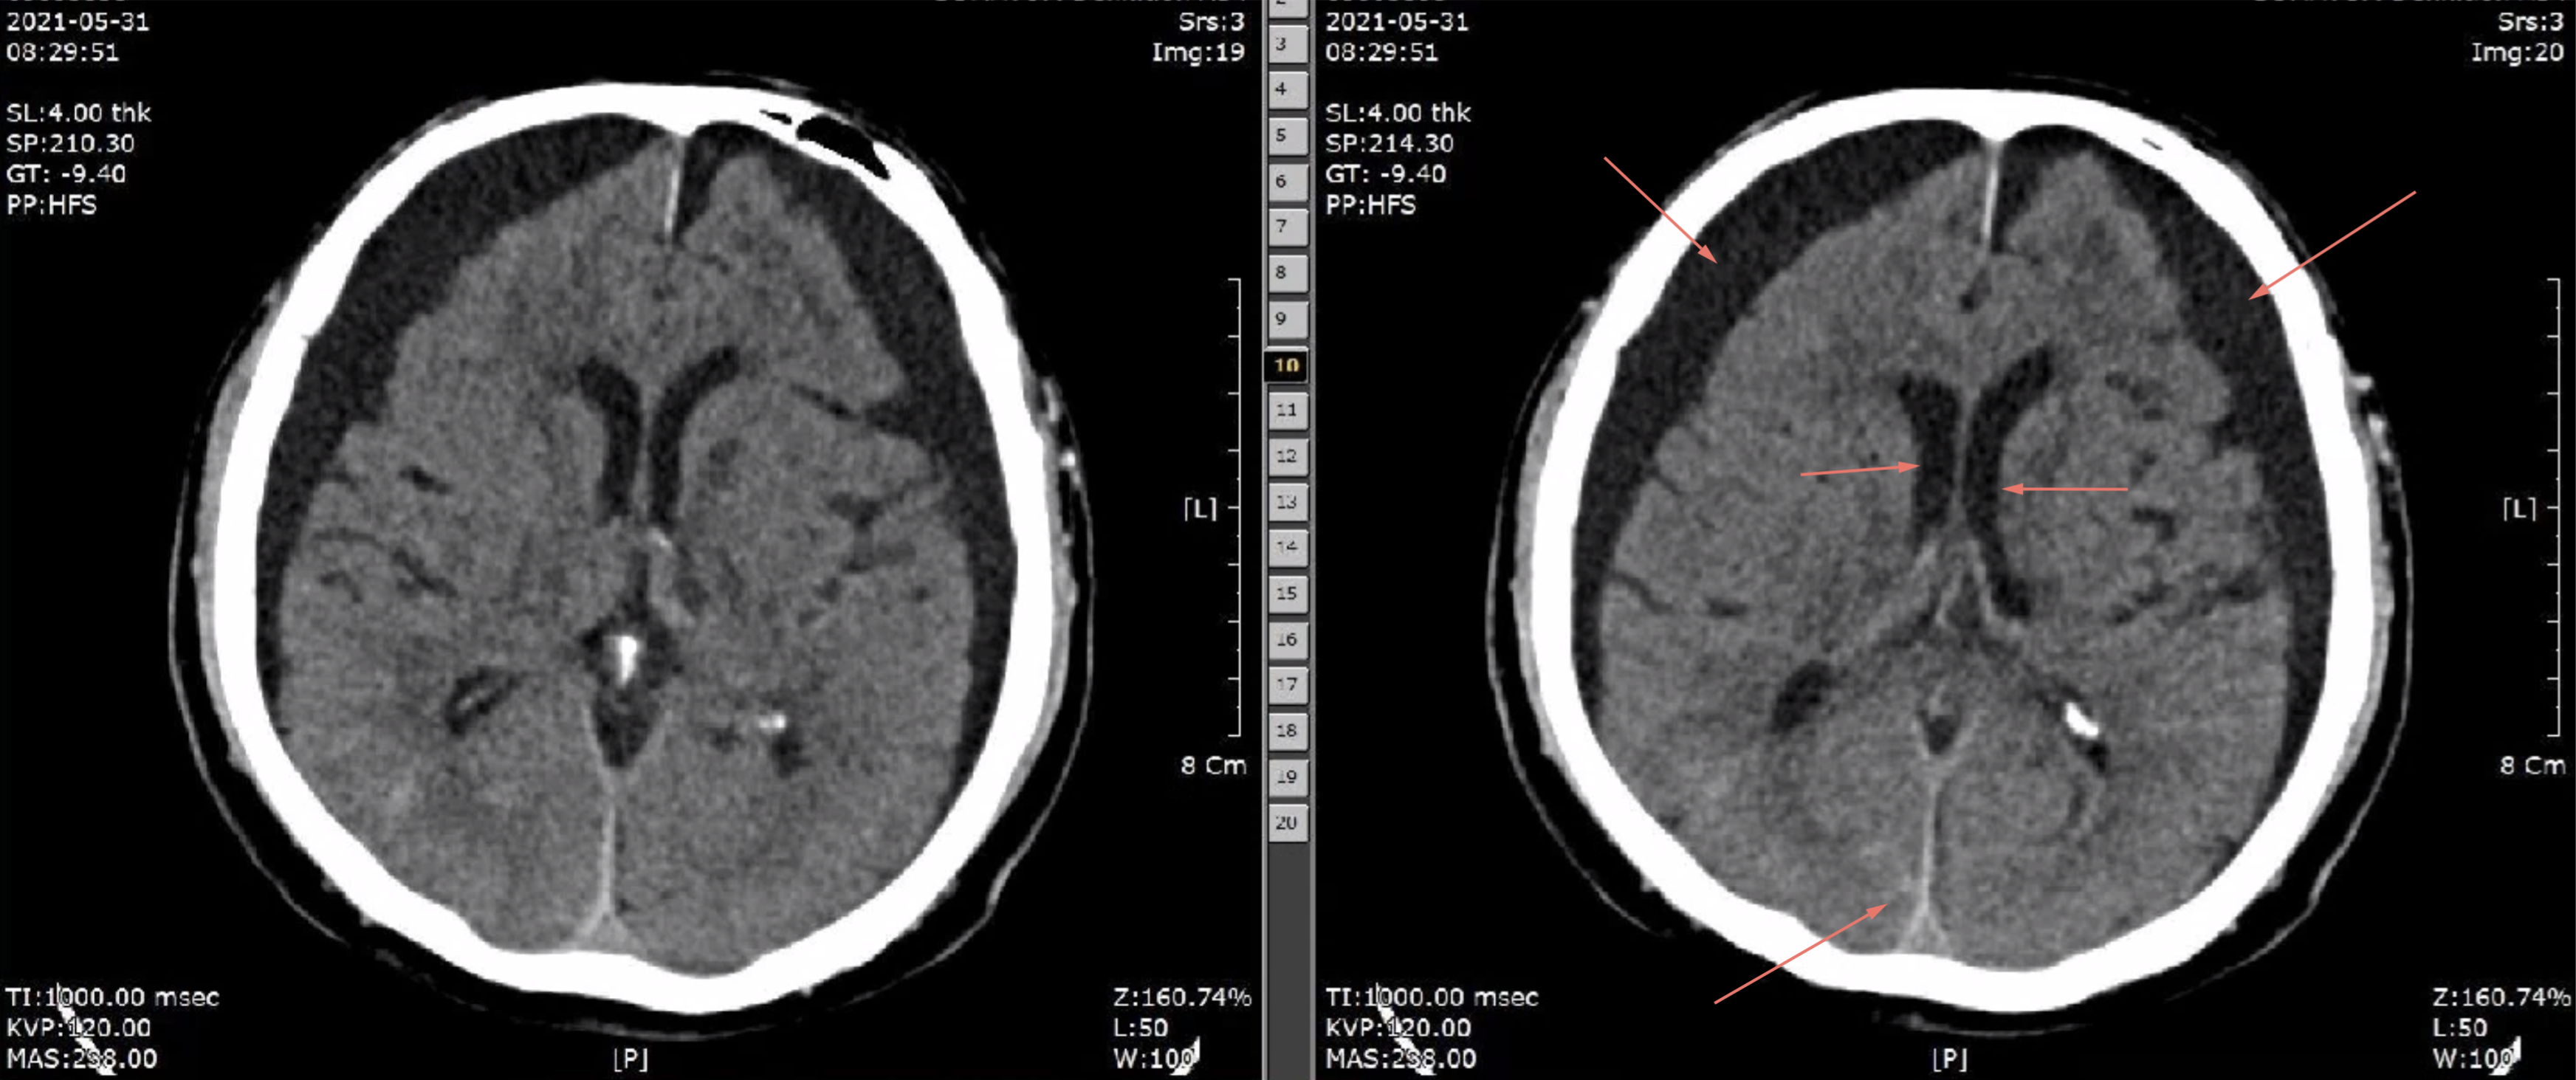

prior right hemiplegia d/t ICH, left thalamic c IVH 2020.2.6.

Acute infarction, Lt. cerebellum

SDH, both cerebral convexity, falx and tentorium